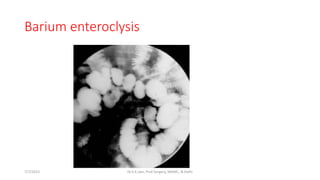

Barium enteroclysis

7/7/2015 Dr.S.K.Jain, Prof Surgery, MAMC, N.Delhi

Barium enteroclysis 7/7/2015 Dr.S.K.Jain,Prof Surgery, MAMC, N.Delhi